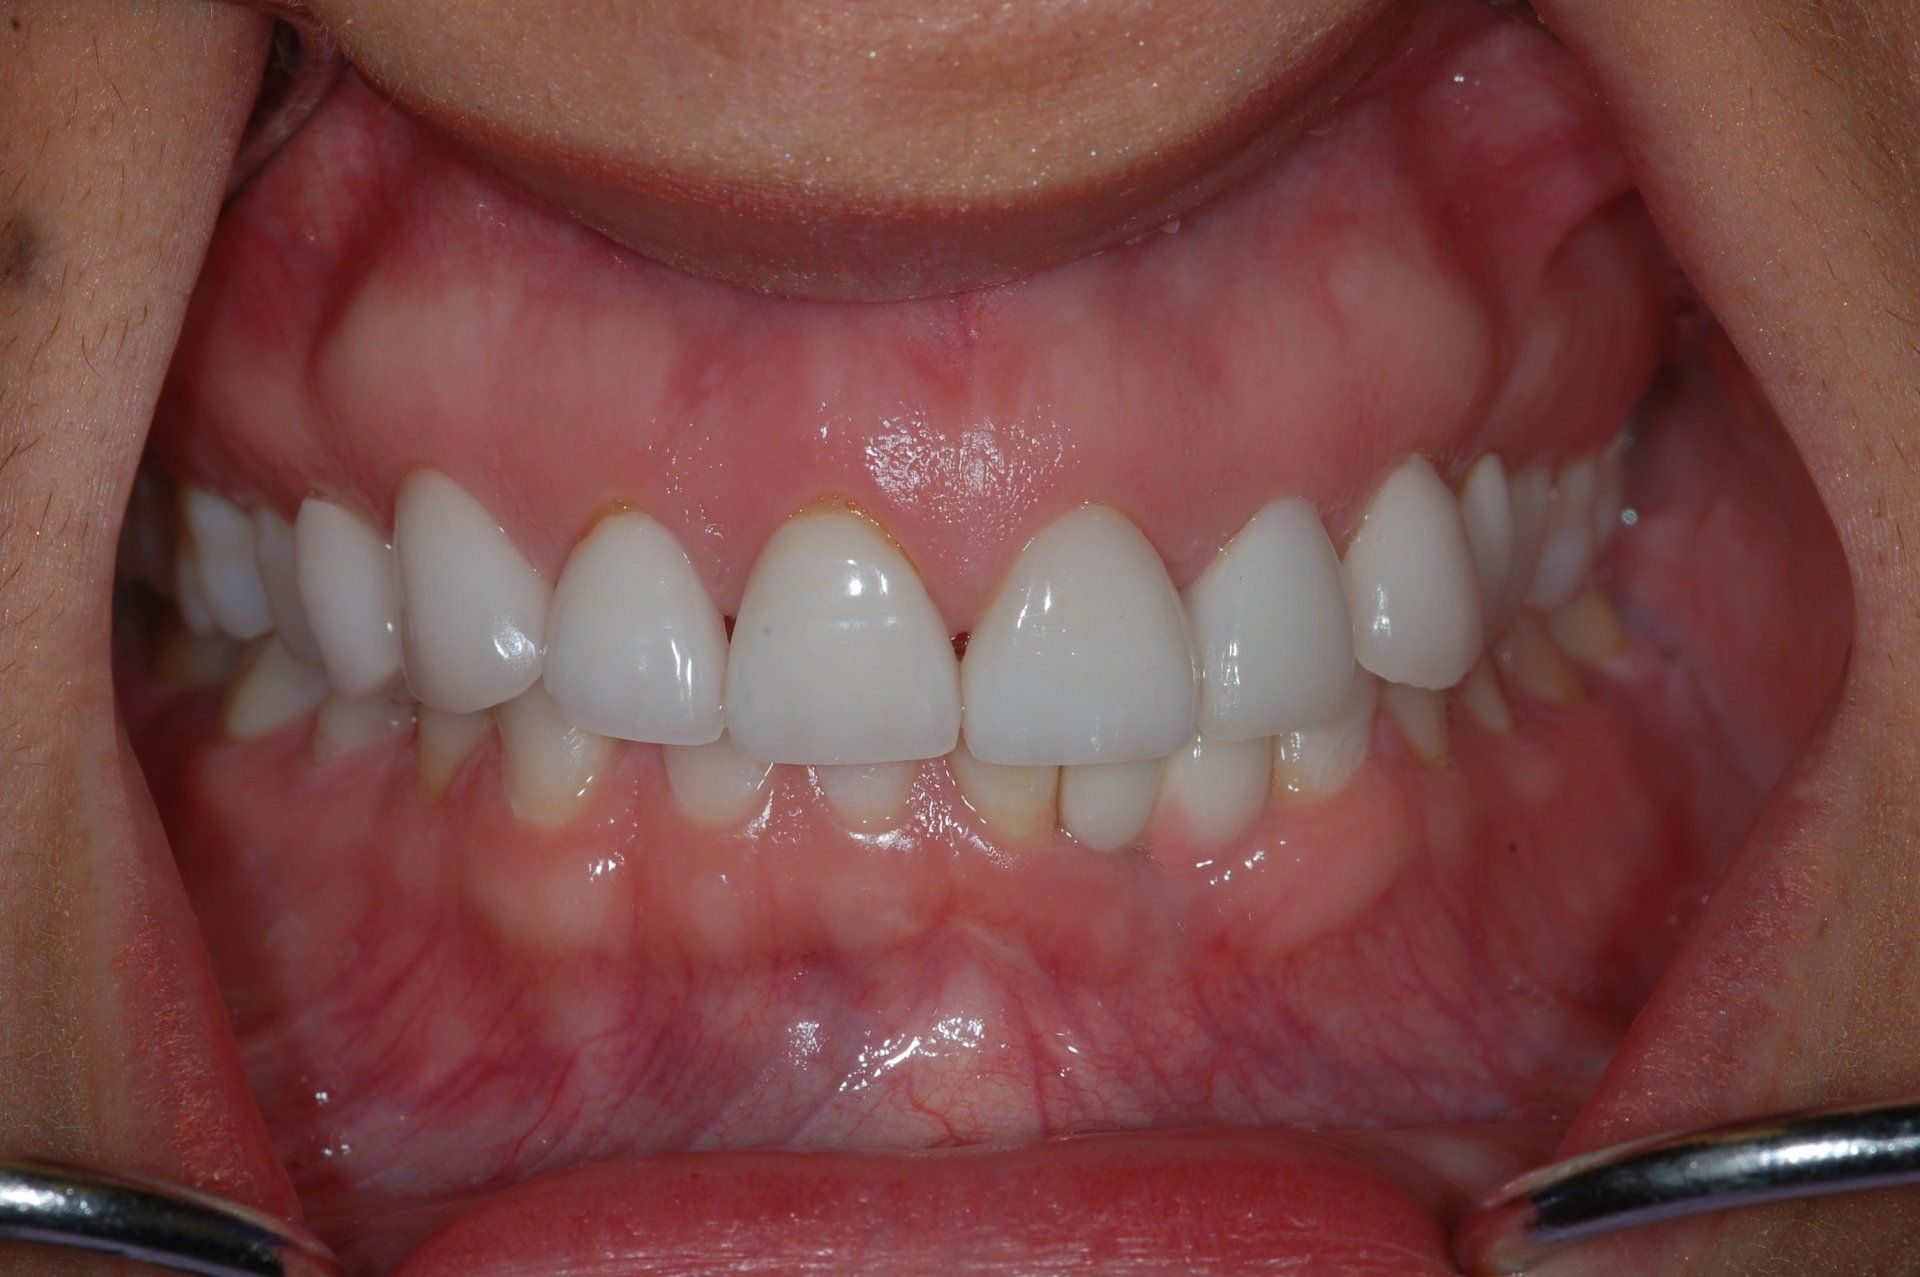

Single Porcelain Crown

Discoloured root canal treated tooth restored with a crown. You can hardly tell!